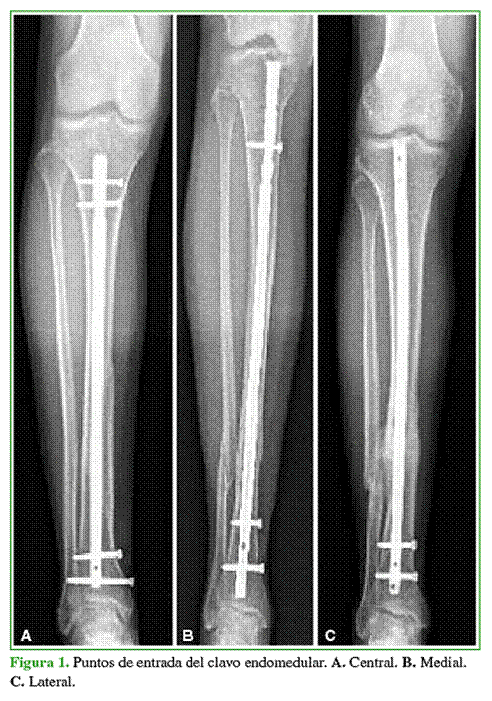

Para este procedimiento se trazó una línea vertical recta desde el punto medio de las espinas tibiales hasta el extremo distal de la tibia, por encima de la articulación tibio-astragalina (Figura 2), luego, se observó la desviación de la fractura y se la clasificó en: varo, valgo o neutra, valoración que se realizó trazando una línea recta desde las espinas tibiales hacia el centro de la diáfisis tibial y luego otra línea recta desde este último punto hasta el extremo distal de la tibia sin tener en cuenta, en este momento, los grados de desalineación.

A los ocho meses de la cirugía y con las fracturas ya consolidadas, se realizó nuevamente la medición para valorar la alineación de la fractura, de la misma manera que en el período posquirúrgico inmediato; en esta ocasión, teniendo en cuenta los grados de desalineación de la fractura en el plano coronal, clasificados en: varo, valgo y neutro (Figuras 3-5).